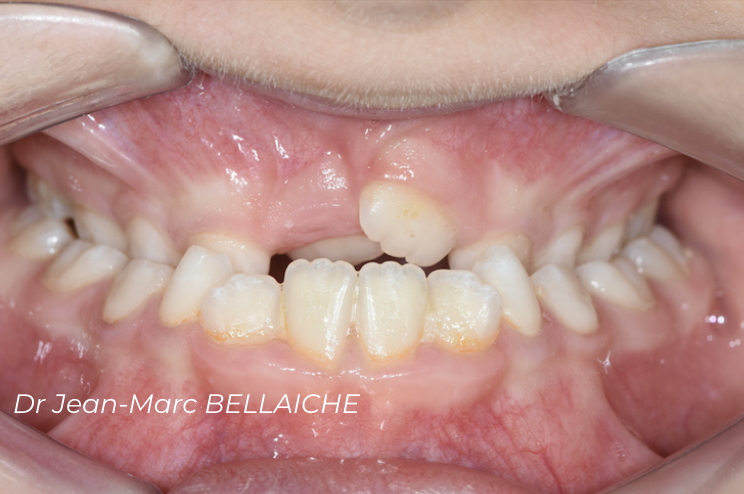

Cas 2 : Encombrement dentaire sévère

Situation "Avant Traitement" : cas d'encombrement associé à un recouvrement excessif des incisives supérieures sur les inférieures empêchant le déroulement normal des fonctions et pouvant être à l'origine de "déchaussements".